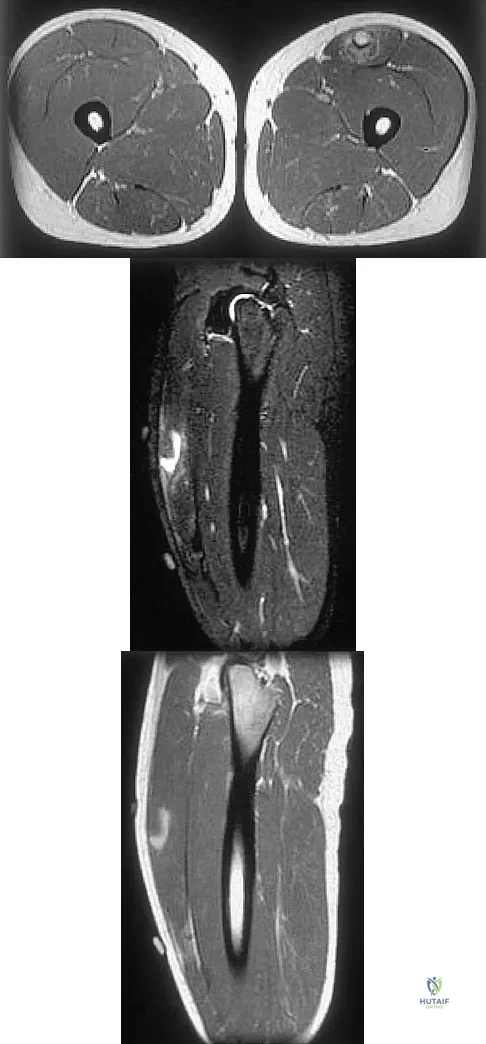

Figures 34a through 34c show an axial proton density (spin echo long TR, short TE) image, a sagittal inversion recovery (STIR) image, and a sagittal T1-weighted (short TR, short TE) image of the left thigh. What is the most likely diagnosis?

Explanation